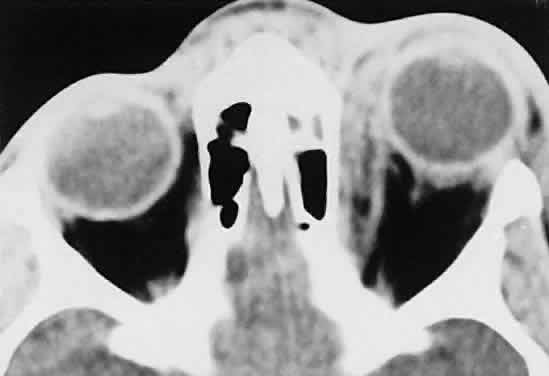

American cases, but invasion of the orbit from the sinuses may occur42,43 (Fig. 4).  Fig. 4. Burkitt's lymphoma involving the posterior ethmoids, skull base, and

both orbital apices in a 5-year-old boy. Fig. 4. Burkitt's lymphoma involving the posterior ethmoids, skull base, and

both orbital apices in a 5-year-old boy.

|